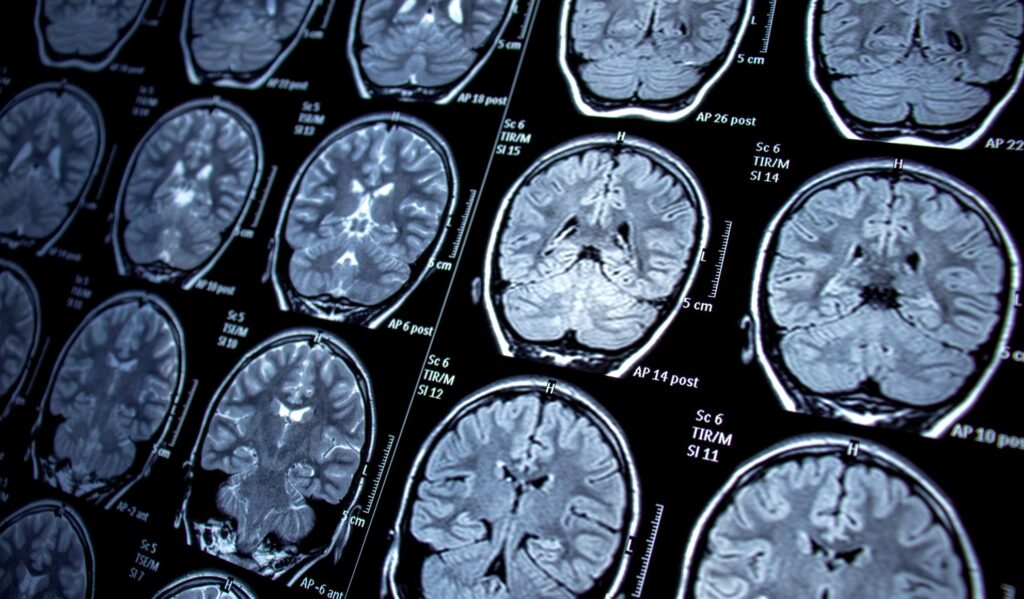

Neurological conditions can complicate daily life. They can complicate movement, memory, and speech, affecting millions of people worldwide.

These conditions affect the brain, spinal cord, and nerves, which are important parts of the body that allow us to function normally.

What are neuromuscular and neurological disorders?

Let’s begin at the beginning. Neurological and neuromuscular disorders are illnesses that affect the way your brain, nerves, and muscles communicate with each other.